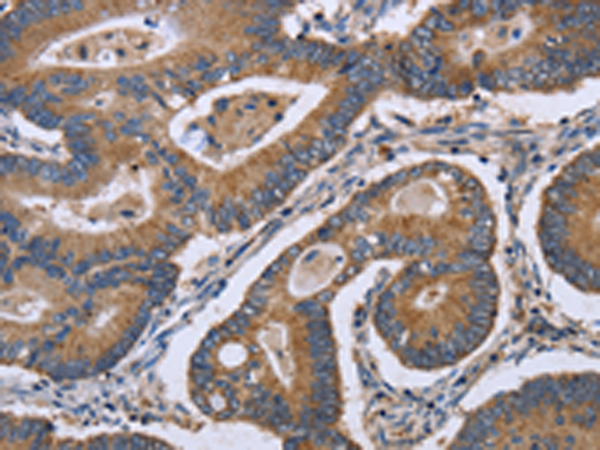

分类: 科研抗体货号: P01330别名: EL; EDL; PRO719应用: IHC反应种属: Human